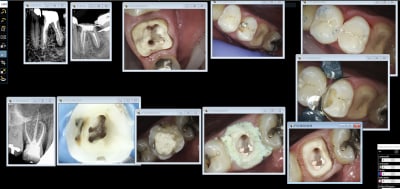

IC ceram 23 + stellite.

Idem que Chicot: Oneshot mais avec un peu plus d’éléments : 3IC, 8 CCM, 1 Stelitte. Aucune retouche autre qu’occlusale. Même Labo, c’est basique mais efficace

Pas mal. Attachements + augmentation de DV en plus.